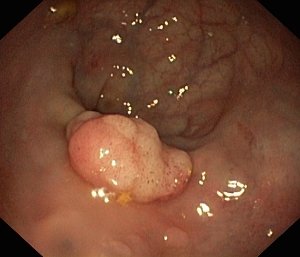

Колоректальный рак чаще всего развивается как перерождение аденоматозных (железистых) полипов.

При наличии описанных выше жалоб, а также пациентам, принадлежащим к группе высокого риска по заболеванию колоректальным раком, проводится дообследование. Наиболее информативным и общепринятым методом служит колоноскопия – эндоскопическое исследование просвета толстой, прямой кишки и части тонкой кишки. Все патологические измененные ткани и полипы будут либо полностью удалены при колоноскопии, либо от них будут взяты кусочки и отправлены на гистологическое исследование. Если образование находится на широком основании или не может быть безопасно удалено при колоноскопии, врач рассмотрит вопрос о проведении хирургического вмешательства.

Основным скрининговым исследованием у пациентов старше 50 лет со средней степенью риска является колоноскопия. При наличии полипов или другой патологии в толстой и прямой кишке регулярность исследований может возрастать до ежегодных или каждые 3-10 лет. Оценивая степень риска развития колоректального рака у пациентов с заболеваниями кишечника, врач принимает решение о частоте проведения исследований индивидуально для каждого больного.